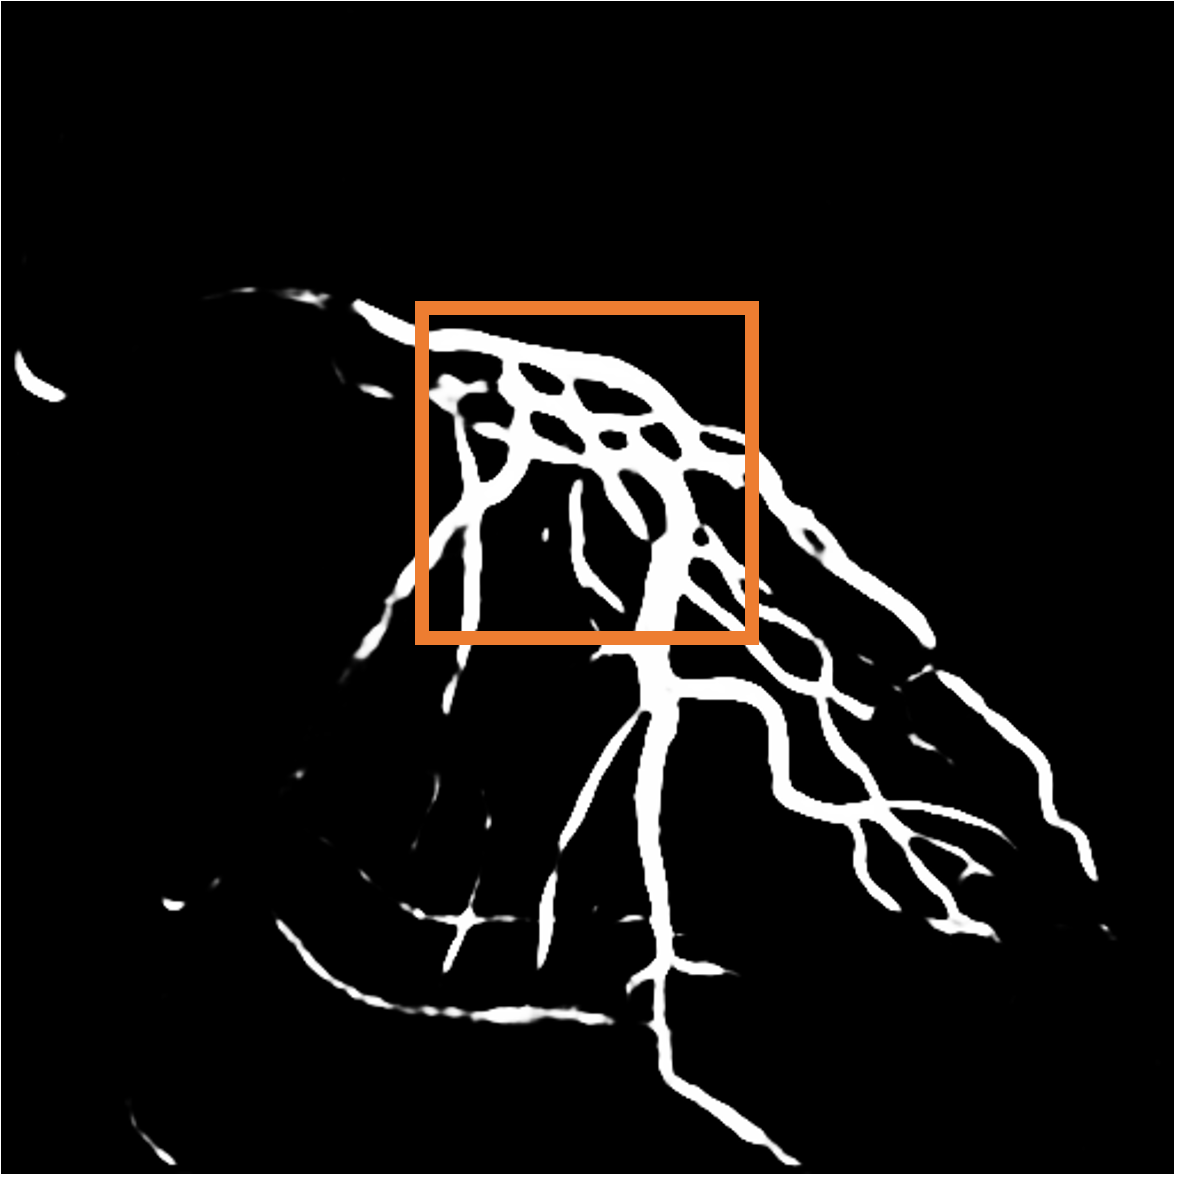

Layer separation bootstrapping. To validate the effectiveness of the layer separation bootstrapping, we train foreground and background canonical images using the same representation. The results are shown in Tab. 2, where optimizing both foreground and background canonical images simultaneously leads to a decrease in the Dice score by 0.0877. The comparison is shown in Fig. 9 (a), where the orange area indicates the difference between without and with Layer separation bootstrapping. The bottom-right corner shows a zoom-in patch, highlighting the significant effect of the bootstrapping step.